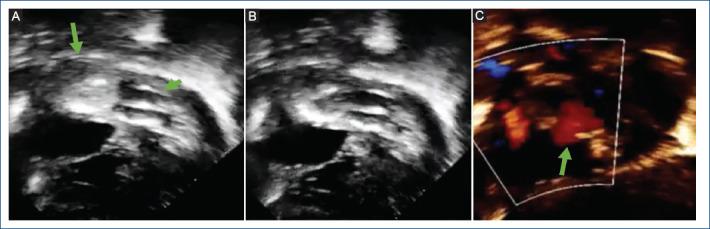

双“动态”球囊房间隔造口术。针对房间隔增厚病例对拉什金德医生技术的新改良。

Double "dynamic" balloon atrial septostomy. New modification of Dr. Rashkind's technique for cases with thickened interatrial septum.

Balloon atrial septostomy (BAS) is a palliative procedure mainly for newborns with transposition of the great arteries, currently, this procedure has a class IA recommendation. However, in some cases, this procedure does not achieve an adequate interatrial defect, due mainly to a thickened interatrial septum, this situation led to the development of various techniques to tackle this problem. Therefore, we made a modification to the original technique using two balloons simultaneously instead of one. The objective of this study is to analyze the results of this new modification to the traditional technique (with one balloon) as an alternative for cases with thickened interatrial septum.

Six patients were identified (median age 35 days, median weight 3.4 kg, median size of atrial septal defect before procedure 2.6 mm). All patients underwent to this modification of the BAS with good results and without complications. The modification has some advantages: including to avoid the using of cutting devices or stent placement. In addition, we share the description of this new technique, titled: double "dynamic" BAS.

球囊房间隔造口术(BAS)是一种主要用于大动脉转位新生儿的姑息性手术,目前该手术有IA类推荐。然而,在某些情况下,该手术无法形成足够的房间隔缺损,主要原因是房间隔增厚,这种情况促使人们开发各种技术来解决这个问题。因此,我们对原技术进行了改进,同时使用两个球囊而非一个。本研究的目的是分析这种对传统技术(使用一个球囊)的新改进在房间隔增厚病例中的应用效果。

共确定6例患者(中位年龄35天,中位体重3.4kg,术前房间隔缺损中位大小2.6mm)。所有患者均接受了这种改良的BAS,效果良好且无并发症。该改良有一些优点:包括避免使用切割装置或放置支架。此外,我们分享了这项新技术的描述,名为:双“动态”BAS。